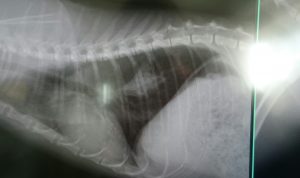

このデカ忌々しいやつがない!↓

ほうら!

どうだ!うちのおとめはすごいだろう!(σ≧▽≦)σ

「消えた!!」

「ない!!消えた!!」

「すごいですよ、どの先生が見ても、これが転移巣だとは判断がつきにくいか、分からない程です」

「いや、これはすごいですよ」